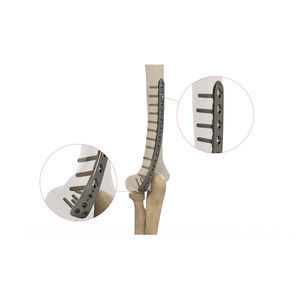

穴の数: 10, 18 unit

... 上腕骨遠位後外側ロックプレート 8ホール 左 上腕骨遠位後外側ロックプレート 左10穴 上腕骨遠位後外側ロックプレート 12 左穴 上腕骨遠位後外側ロックプレート 14 左穴 上腕骨遠位後外側固定プレート 8穴 右 上腕骨遠位後外側ロックプレート 10ホール 右 上腕骨遠位後外側固定プレート 12穴 右 上腕骨遠位後外側ロックプレート 14穴 右 ...